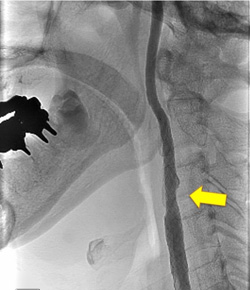

写真左:術前頚動脈狭窄所見

写真右:術後所見 外科手術によって頚動脈狭窄は改善している